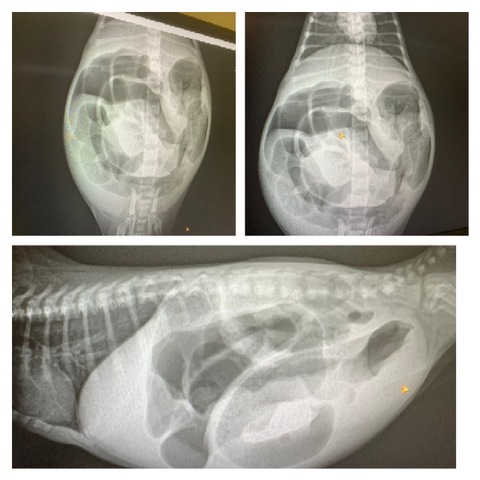

離乳期になっても排便がうまくできず、体重も兄妹の約半分で未熟でした。

何度か通院し、詳しい検査で自力で排便できないことがわかりました。

タイプ4鎖肛です。

300g台のこねこくん…難しい状況とは覚悟の上で…

望みをかけ、人工肛門での処置に踏みきりました。